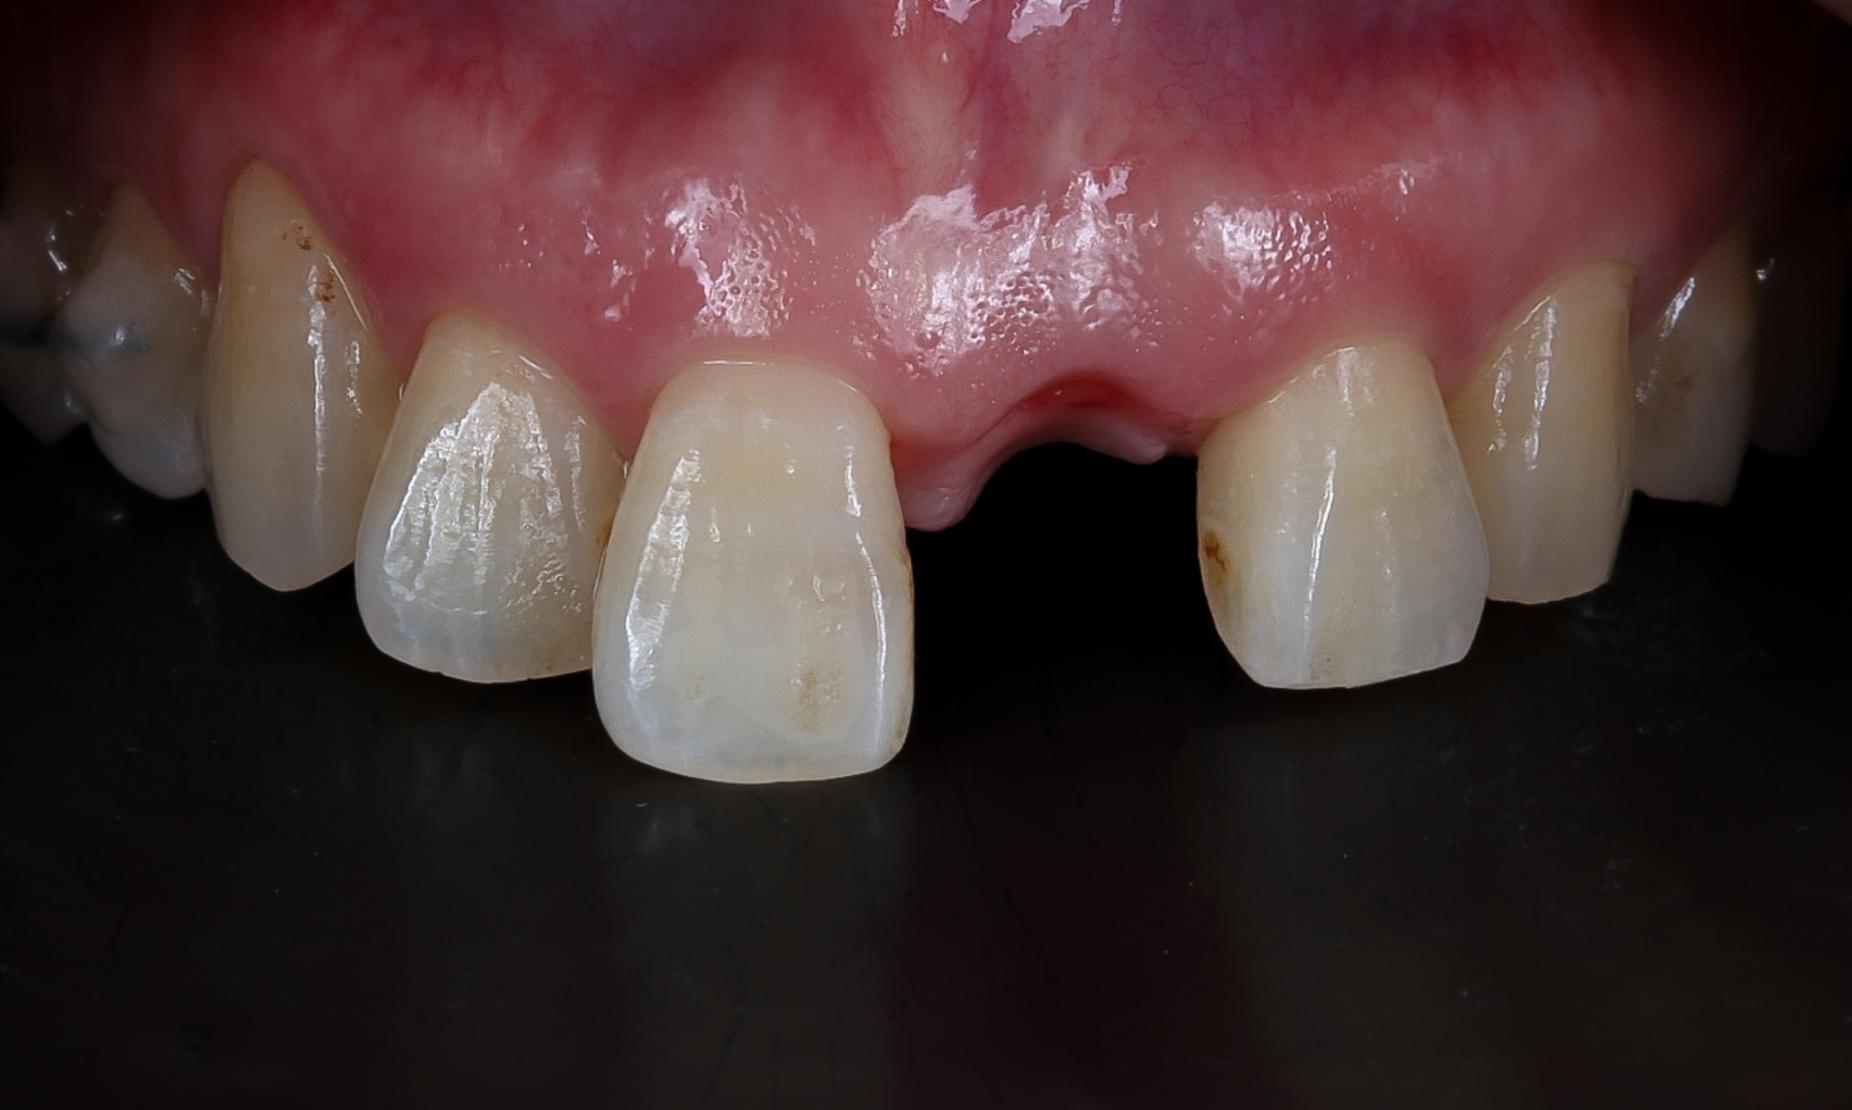

初診時のお口の状態を確認したところ、左右の前歯のスペースが揃っていないことが判明しました。このままでは左側のインプラントを挿入すると不自然に大きな歯となり、審美性が損なわれるリスクがありました。

初診時の歯ぐきの状態。ちょうどよく見えるがこのまま埋入すると審美審美性が損なわれてしまう。